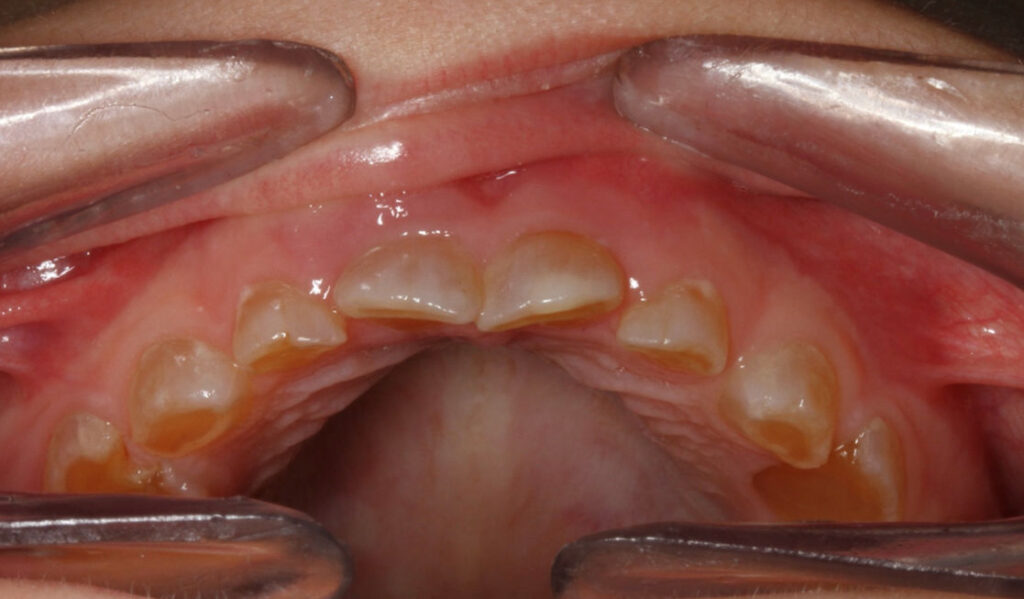

9-year-old girl undergoing recall exam

An asymptomatic 9-year-old girl undergoing a recall exam.